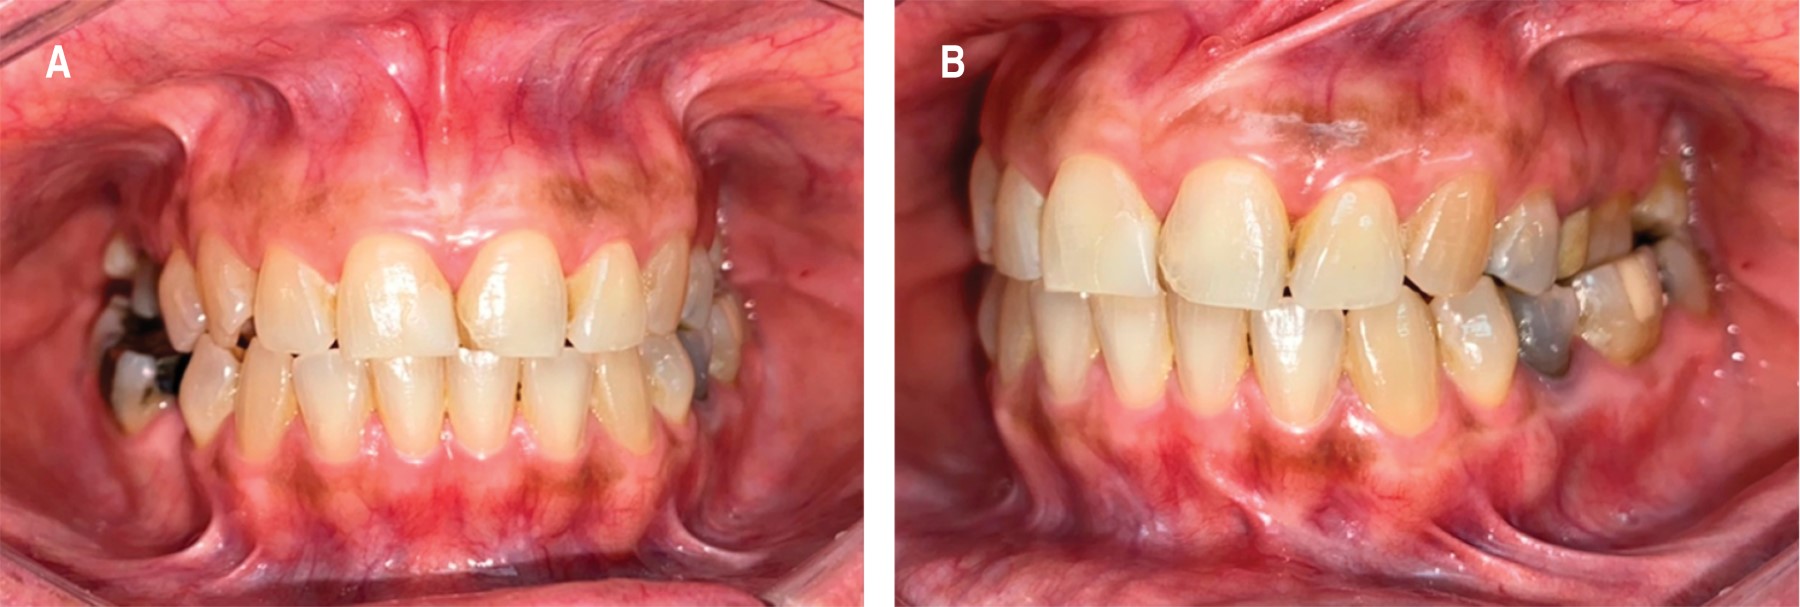

Al examen físico extrabucal se observan tercios faciales aparentemente simétricos, al examen intrabucal se evidencian múltiples restauraciones defectuosas, ausencia de órganos dentarios 1.8, 2.8, 3.8, 4.5 y 4.8. A nivel de 3.5 y 36 se observa restauración de tipo provisional. Se observa un aumento de volumen de 7.5 mm de altura × 3.5 mm de ancho, en zona mandibular premolar (entre 3.4 y 3.5) (Figura 1), normocrómico, normotérmico, firme a la palpación, se realizaron pruebas de sensibilidad dentaria en órganos dentarios 3.4-3.5-3.6, obteniendo resultados negativos para todas las pruebas realizadas (frío, calor, percusión vertical, percusión horizontal).

Figura 1